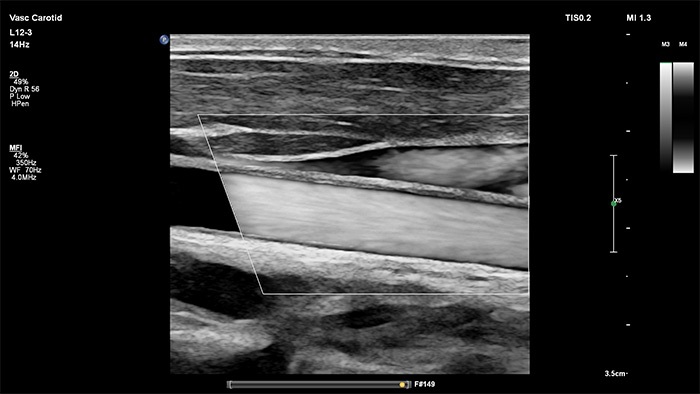

In der Bildverarbeitung der jüngsten Generation von Philips wird die Gefässdiagnostik durch die exzellente Abgrenzung der Gefässe und genaue Erkennbarkeit der Plaque-Beschaffenheit, auf eine neue Ebene gehoben. Auch bei technisch schwierigen Gefässuntersuchungen erhöht XRES Pro die Diagnosesicherheit durch die Reduktion von Schleiern und Artefakten.